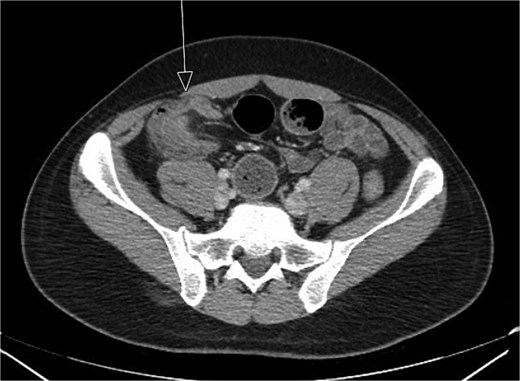

CT imaging (Figs 1 and 2) revealed an abnormal ileocolic configuration with intussusception of the distal ileal loop through the cecum. At this point, the general surgery team was consulted for immediate evaluation. Due to the history, physical exam, and findings identified on CT imaging, the patient was recommended to undergo exploratory laparotomy with intent, at minimum, to reduce the intussusception and likely perform a segmental small bowel resection to address his small bowel obstruction. Right hemicolectomy, however, was also discussed due to the patient’s family history of colon cancer to relieve the intussusception, which was causing a high-grade small bowel obstruction. During surgical exploration, the ileum was fixed within the colon, and the intussusception could not be reduced with gentle manipulation. This area of the ileum was significantly firmer than other areas, which was concerning for an ileal mass. The decision was made to resect this portion of the ileum and perform a right hemicolectomy with ileocolonic side-to-side anastomosis. The specimen was sent to pathology for further investigation. Postoperatively, the patient was hospitalized for 3 days for pain control and monitoring. He recovered in the hospital without further incident and was discharged on day 3 prior to the finalization of his pathology report.

Initial CT imaging, coronal cut, showed an abnormal ileocolic configuration with intussusception of the distal ileal loop through the cecum.